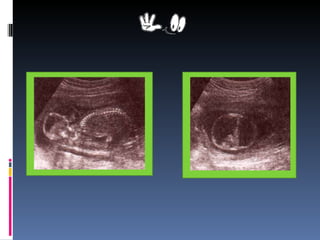

Introducción Las malformaciones congénitas son defectos morfológicos intrínsecos  producidos durante el proceso de desarrollo y que se presentan en el  momento del nacimiento. Muchos son los factores asociados a estas alteraciones y estas no solo tienen una repercusión en el núcleo familiar sino también sobre la sociedad; revistiendo singular importancia detectar los factores que más se relacionan con las mismas con la intención de  reducir su representación. Las malformaciones congénitas ocupan uno  de los primeros lugares de enfermedades crónicas que se detectan en neonato . Este tema es muy amplio pero nos vamos a centrar en tratar las malformaciones desde la etapa prenatal (7 meses)  hasta el primer mes de su nacimiento.

Marco Teórico Concepto._   Las malformaciones congénitas son deficiencias estructurales presentes al nacer y producidas por una alteración en el desarrollo fetal. Estos defectos  aparecen  en el recién nacido debido muchas veces por  trastornos genéticos, es decir a las alteraciones que sufren la estructura cromosómica del niño.